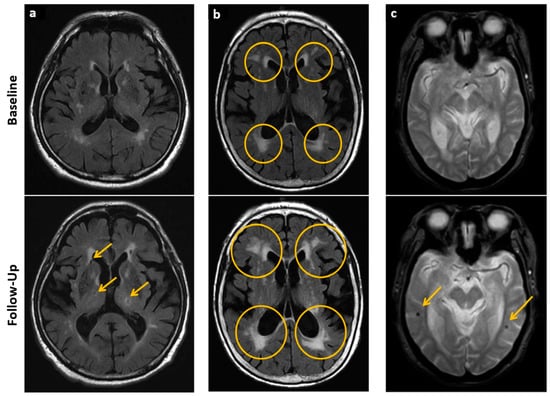

- Biessels, G.J.; Reijmer, Y.D. Brain Changes Underlying Cognitive Dysfunction in Diabetes: What Can We Learn From MRI? Diabetes 2014, 63, 2244–2252. [Google Scholar] [CrossRef]

- Fox, L.A.; For the Diabetes Research in Children Network (DirecNet); Hershey, T.; Mauras, N.; Arbeláez, A.M.; Tamborlane, W.V.; Buckingham, B.; Tsalikian, E.; Englert, K.; Raman, M.; et al. Persistence of abnormalities in white matter in children with type 1 diabetes. Diabetologia 2018, 61, 1538–1547. [Google Scholar] [CrossRef]

- Potter, G.M.; Doubal, F.N.; Jackson, C.A.; Chappell, F.M.; Sudlow, C.L.; Dennis, M.S.; Wardlaw, J.M. Enlarged Perivascular Spaces and Cerebral Small Vessel Disease. Int. J. Stroke 2015, 10, 376–381. [Google Scholar] [CrossRef] [PubMed]

- Ferguson, S.C.; Blane, A.; Perros, P.; McCrimmon, R.J.; Best, J.J.; Wardlaw, J.; Deary, I.J.; Frier, B.M. Cognitive ability and brain structure in type 1 diabetes: Relation to microangiopathy and preceding severe hypoglycemia. Diabetes 2003, 52, 149–156. [Google Scholar] [CrossRef]